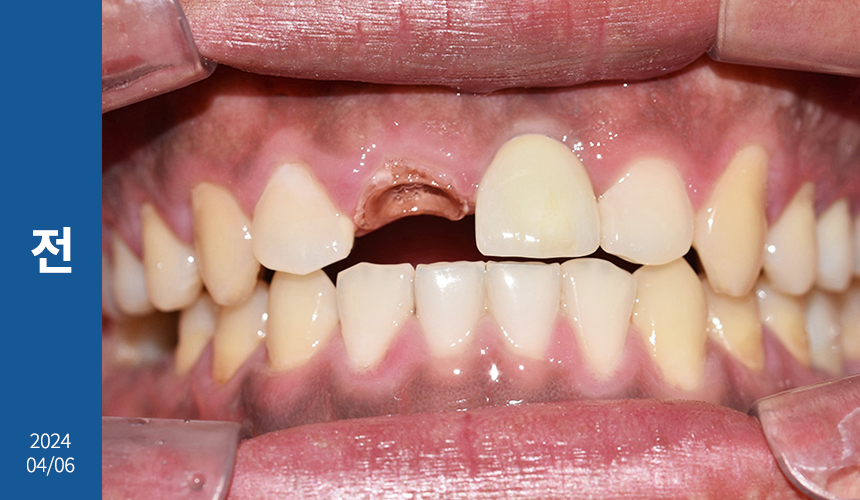

상담을 할 때 환자분께서

부드러운 음식만 주로 먹게 될 만큼

앞니가 많이 불편해요.

라고 하셨는데요.

X-ray 상 앞니 손상과 치근 염증이

심하다는 결과를 봐서는 발치가 필요해 보였으며

좌측 하악 어금니도 뿌리 밑에 염증이 생겨

치아 보존이 힘든 상황이었습니다.

그만큼 치아 강직과 만성 복합치주염으로 인한

난발치 상황이었죠.

우측도 파열돼있었지만

우선 치주 치료를 하면서 지켜봐도

좋을 것 같다는 판단이 들었습니다.